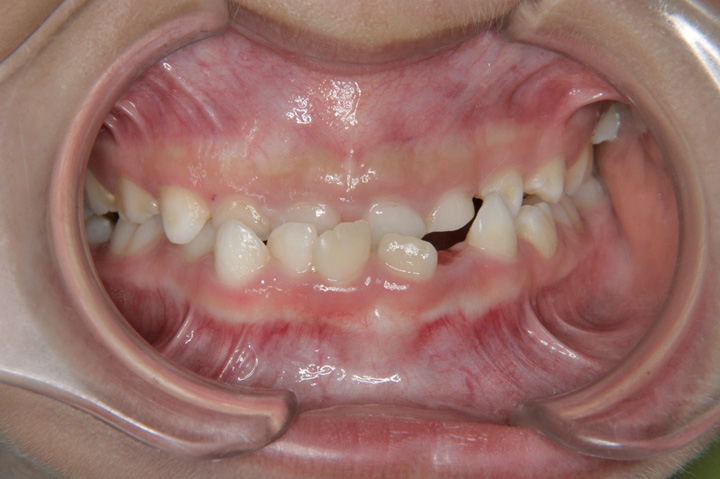

下顎前突(受け口)

下顎前突(受け口)とは、下の歯が上の歯より前に出て、噛み合わせが反対になった状態を言います。 下顎前突の人は、食べ物がよく咬めないだけでなく、聞きとりにくい話し方になることもあります。お子様の場合、低学年(7~9歳)であっても、受け口と判断される場合は、受診をお勧めいたします。 その時期であれば、比較的良好な治療結果となることが多いと思います。成人の方の治療は可能ですが、側貌で過成長な下顎の状態が残る場合が多く、重度の場合は外科矯正の適用となります。